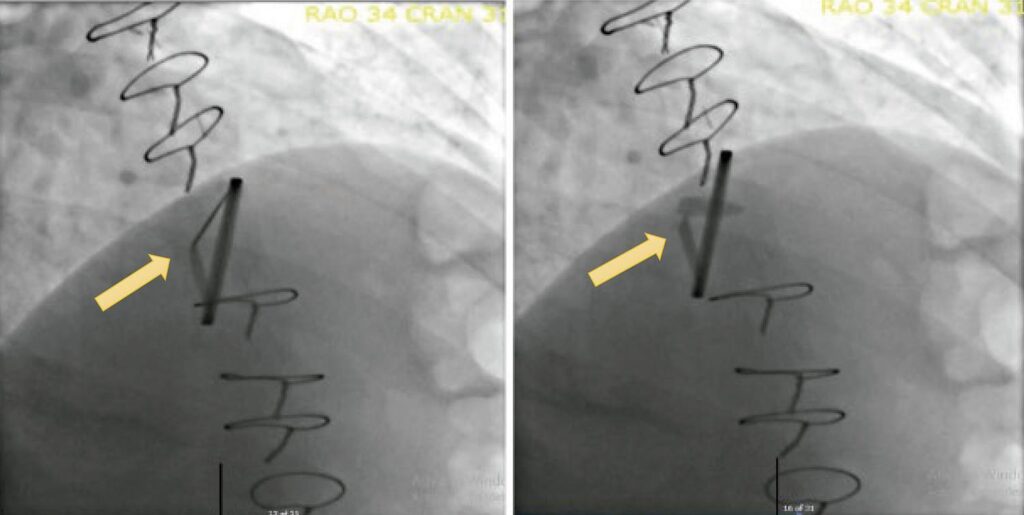

O presente relato apresenta um caso de disfunção de prótese valvular mitral mecânica devido à formação de pannus. Uma mulher caucasiana de 43 anos, com dislipidemia e hipertensão, apresentou endocardite infecciosa da válvula mitral em 04/2022, com infiltração dos folhetos e regurgitação mitral grave. Um ciclo de antibioticoterapia com ampicilina e flucloxacilina foi administrado, sem que nenhum agente fosse identificado em hemoculturas ou exames microbiológicos da válvula explantada. Uma prótese valvar mecânica de disco duplo foi implantada na posição mitral. A paciente foi tratada com antagonista da vitamina K (varfarina, alvo INR 2,5-3,5) e recebeu alta para acompanhamento ambulatorial.